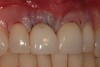

Fig 12. At 8 years post-treatment, the results of the minimally invasive approach remain an ideal esthetic implant placement, without visible damage or scar tissue from the flapless approach or connective tissue graft to thicken the biotype.

Figure 12

At 8 years post-treatment, implant bone levels were maintained as evidenced radiographically (Figure 11), with stable gingival margins and bone levels at the first thread of the fixture. There was minimal visible damage and scar tissue from the surgical approach to implant placement and tissue grafting to thicken the biotype. Despite the potential challenges, the use of growth factor technology and minimally invasive surgical techniques allowed the esthetic treatment goals for this case to be achieved for the long term (Figure 12).